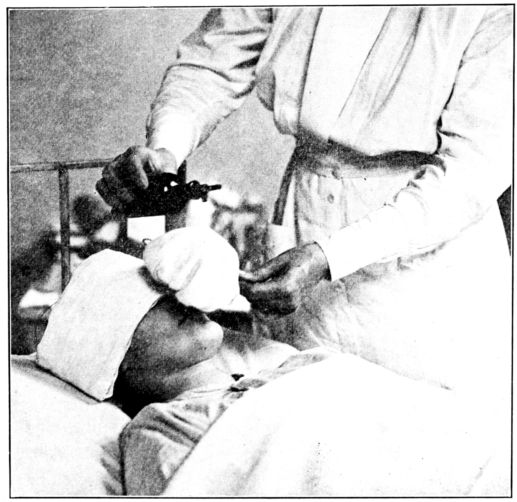

| 103. | Giving chloroform for obstetrical anæsthesia | 287 |

| 104, 105. | Giving ether for obstetrical anæsthesia | 289, 290 |